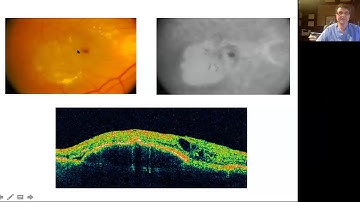

Technical Talk: 3D Semantic Segmentation of Anatomic and Pathologic Features in Retinal OCT Volumes